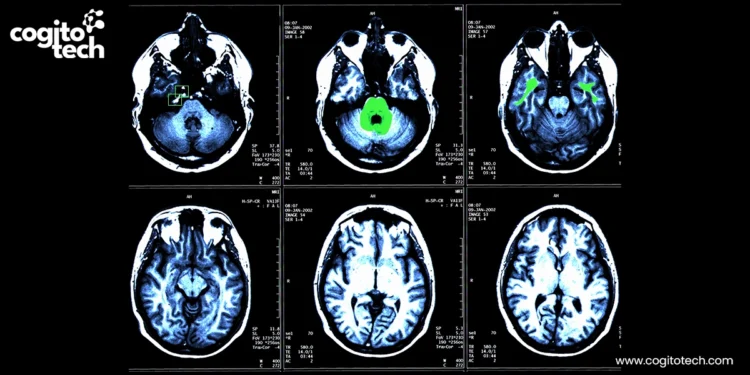

Cardiac imaging annotation

- Cardiac MRI: This involves segmenting the ventricles, atria, myocardium, and pericardial fat, as well as labeling tissue characteristics such as late gadolinium enhancement (LGE) scars. These annotations help AI models analyze cardiac function, fibrosis, and metabolic risk.

Structured labeling of cardiac MRI and late gadolinium enhancement (LGE) images – covering myocardial tissue properties, scar regions, and key anatomical landmarks – supports deep learning models for automated scar quantification, arrhythmia focus localization, and ablation strategy planning. These annotations also enable real-time guidance systems and robotic-assisted interventions by improving anatomical mapping and reducing fluoroscopy exposure. High-quality, clinically validated annotations are critical for training scalable and reliable AI models in electrophysiology imaging applications.